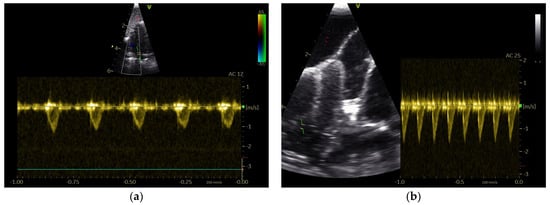

3.1. Shape of PAFP and AOFP